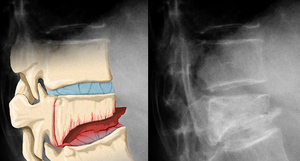

Компрессионный перелом поясничного отдела позвоночника: что это такое? Компрессионный перелом поясничного позвонка представляет собой травму, которая приводит к изменению формы позвонка, а также к деформации поясничной области, что может как увеличивать, так и уменьшать естественную кривизну поясницы.

Когда тело пытается адаптироваться к изменениям в поясничном отделе позвоночника для поддержания вертикального положения, это может привести к искажению кривизны грудного и шейного отделов.

Компрессионная травма поясницы может быть крайне серьезной по двум основным причинам. Во-первых, сама травма может вызывать интенсивную боль, которая иногда становится хронической. Во-вторых, повреждение позвонка может негативно сказаться на механике осанки. В большинстве случаев это приводит к увеличению грудного кифоза, что может достигать такой степени, что пациент не в состоянии стоять прямо. Стремясь сохранить возможность передвижения, пациенты с кифозом часто испытывают вторичную боль в области бедер, крестцово-подвздошных суставов и позвоночника. Кроме того, такие пациенты более подвержены риску падений и травм, что увеличивает вероятность получения вторичных повреждений позвоночника и других частей тела.